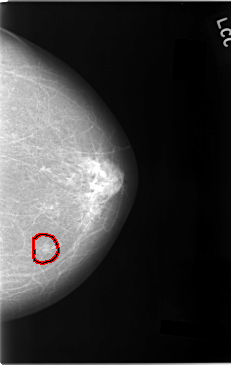

C_0027_1.LEFT_CC

LEFT_CC LINES 5840 PIXELS_PER_LINE 3696 BITS_PER_PIXEL 12 RESOLUTION 50 OVERLAY

FILE: C_0027_1.LEFT_CC.OVERLAY

TOTAL_ABNORMALITIES 1

ABNORMALITY 1

LESION_TYPE MASS SHAPE LOBULATED MARGINS MICROLOBULATED

ASSESSMENT 5

SUBTLETY 4

PATHOLOGY MALIGNANT

TOTAL_OUTLINES 1

BOUNDARY